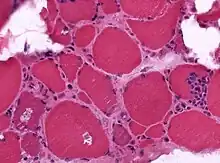

| A muscle biopsy from someone who is diagnosed with myositis. | |

Muscle biopsies are the most reliable tests for diagnosing myositis.[4]